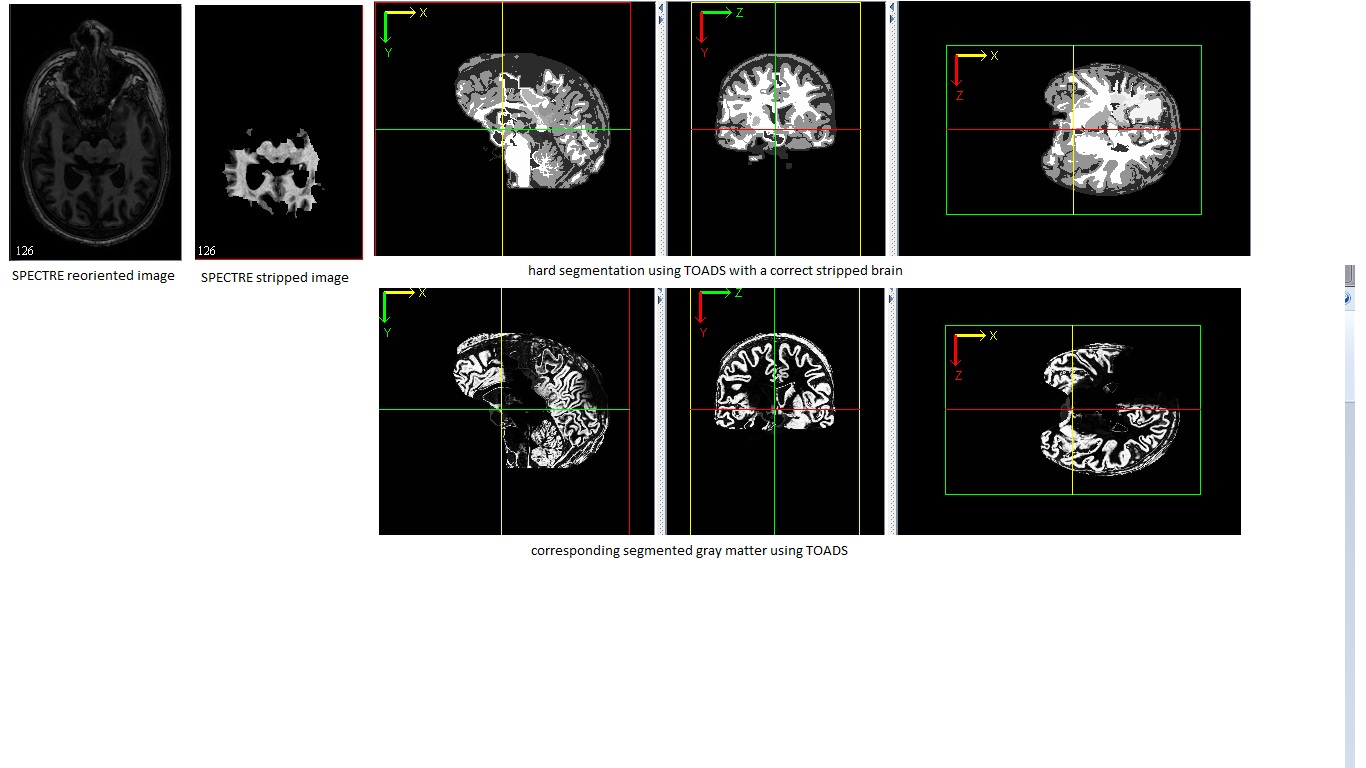

I was trying to use LongCruise pipeline to extract the brain surfaces, but it turned out that in its very first step, SPECTRE failed to extract the brain correctly; some part of the brain is missing. Then I tried my own another brain extraction method and segmented the extracted image using TOADS, it seemed that TOADS had problem too. All I used were default settings. Could anybody tell me what's wrong?

The images are attached.

I think it is clear in the last view that the lower right part of gray matter is definitely lost. I also use FANTASM to segment, the result is attached, looking more reasonable.